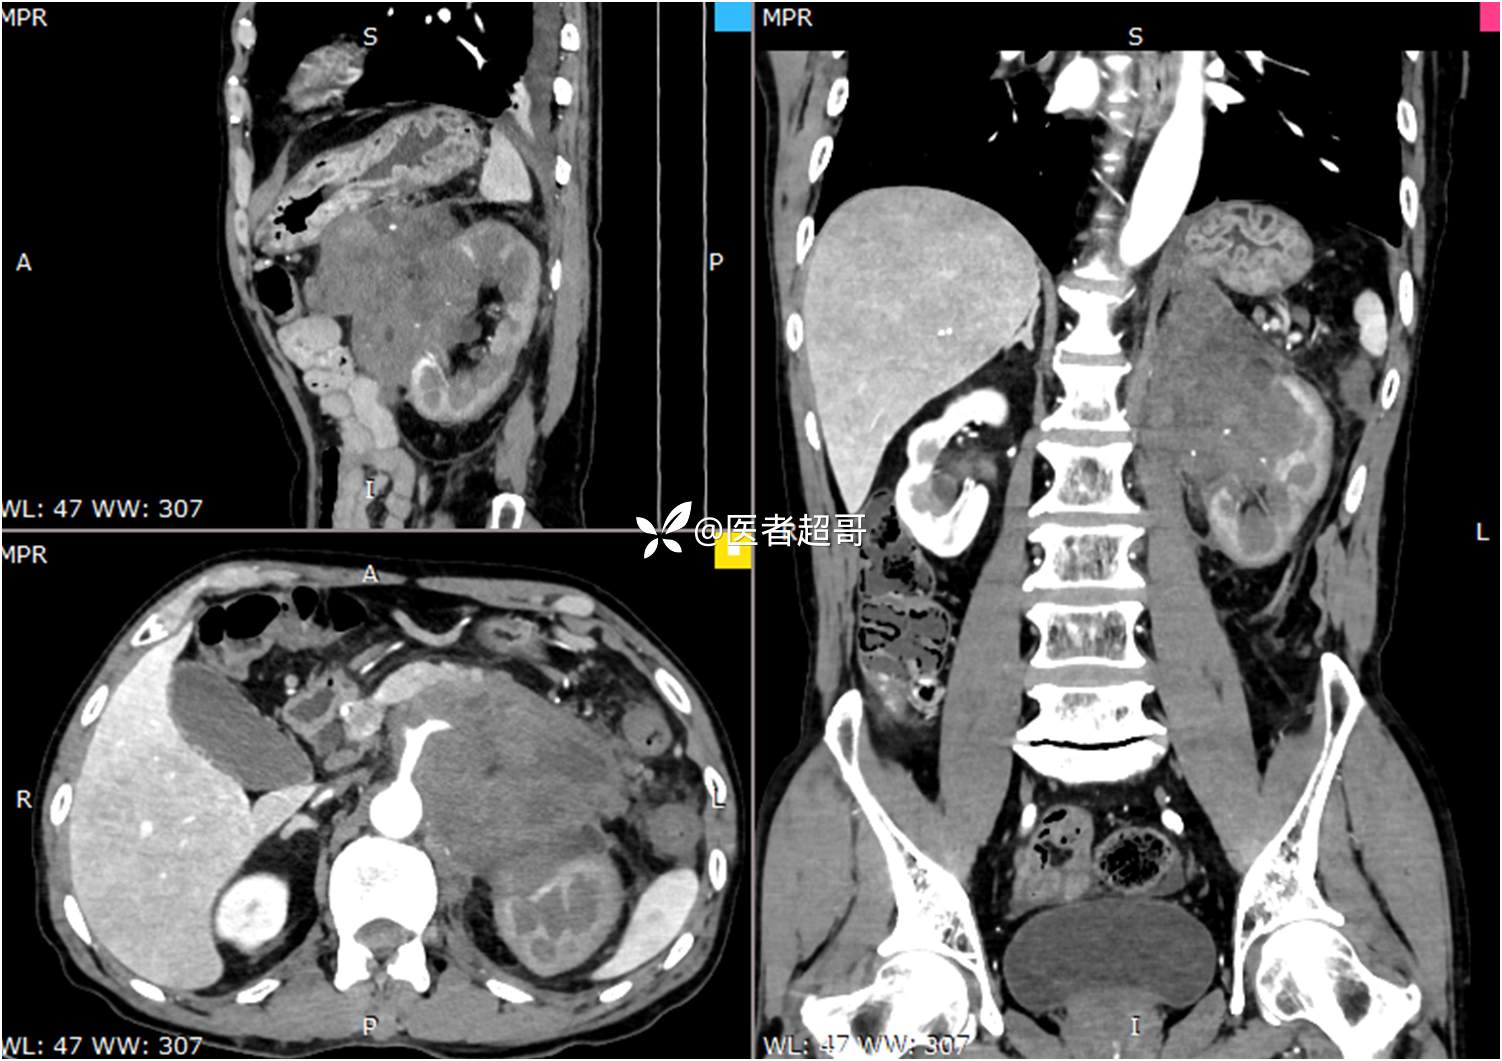

现病史:患者于1月前无明显原因及诱因出现左上腹部疼痛,为间断性疼痛,无恶心、呕吐,无寒战、高热,无腹胀、腹泻等伴随症状,在外未行特殊处理,患者于1周前自觉疼痛加重,为求诊治患者曾就诊于市东城医院,行全腹部强化CT提示:左肾上腺区肿块,符合恶性肿瘤侵犯左肾、胰腺及腹膜后大血管CT表现,行保守治疗,症状缓解,今患者为求进一步诊治,来我院就诊,行腹膜后占位穿刺活检病理提示:(腹膜后占位穿刺)小细胞背景内见细胞浆红染的神经节样细胞,建议到病理科加做免疫组化进一步明确诊断,遂以“腹膜后肿物”收入院,患者自发病以来,神志清,精神可,饮食、睡眠差,大小便正常,体重未见明显改变。